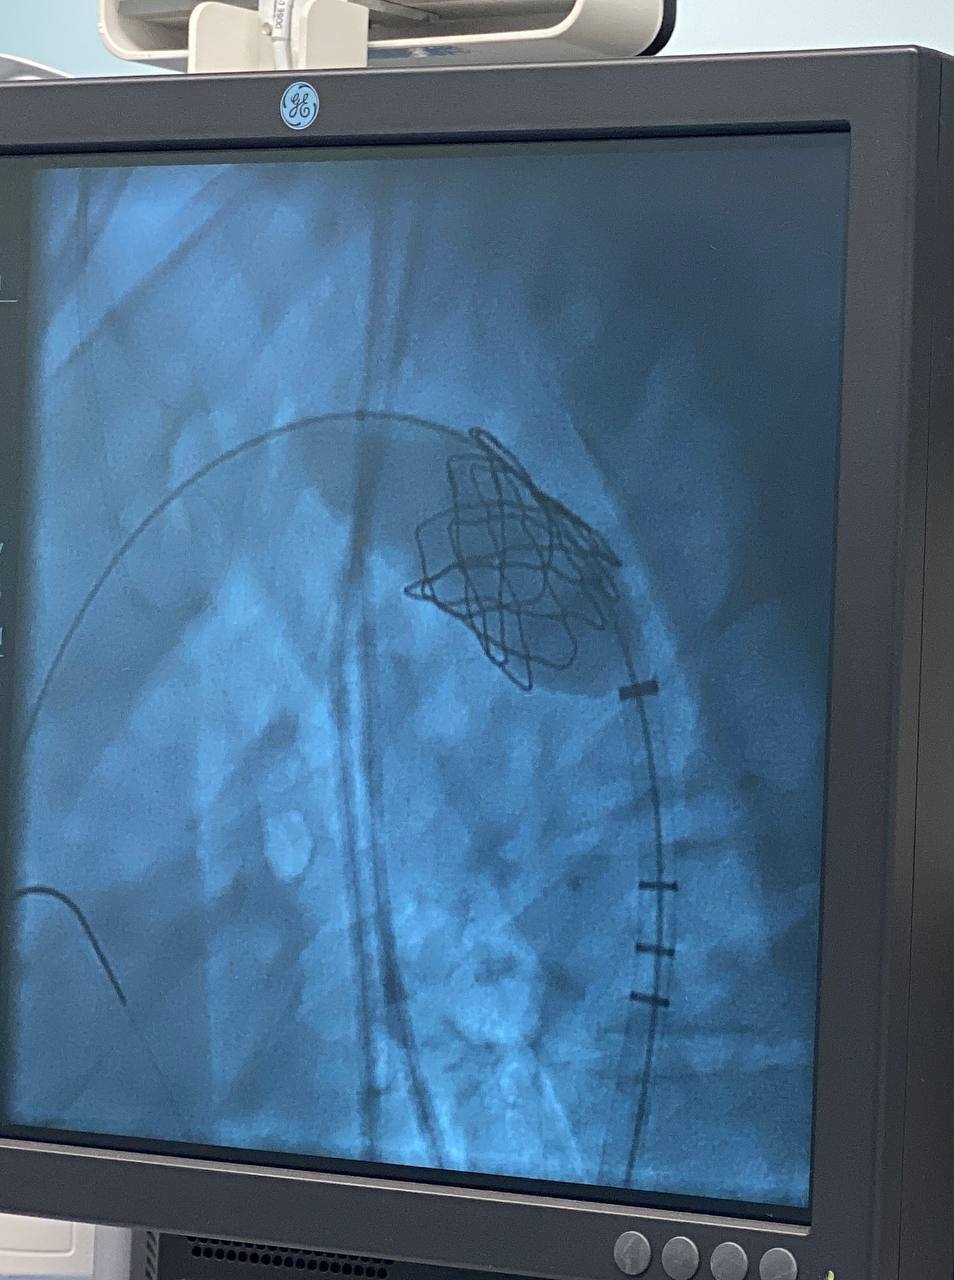

В Югре хирурги спасли подростка от врожденного порока сердца без единого разреза

В Сургуте хирурги окружного кардиологического диспансера устранили 17-летнему подростку врожденный порок сердца без разреза грудной клетки - через прокол в бедренной артерии. Об этом рассказал глава Департамента здравоохранения ХМАО-Югры Роман Паськов.

Поводом для обследования юноши стали обычные на первый взгляд жалобы: парня мучили головные боли и скачки давления. Диагноз оказался серьезным — врожденное сужение аорты, коарктация. В самом узком месте просвет сосуда составлял всего 3 миллиметра.

Медики приняли решение не прибегать к полостной операции. Команда кардиохирургов и рентгенхирургов провела уникальное вмешательство: через прокол в бедренной артерии к аорте подвели стент-графт — металлический каркас, который раскрыли прямо в зоне сужения. Все заняло полтора часа.

Уже на следующее утро пациент смог вставать с постели, а через несколько дней его выписали домой.